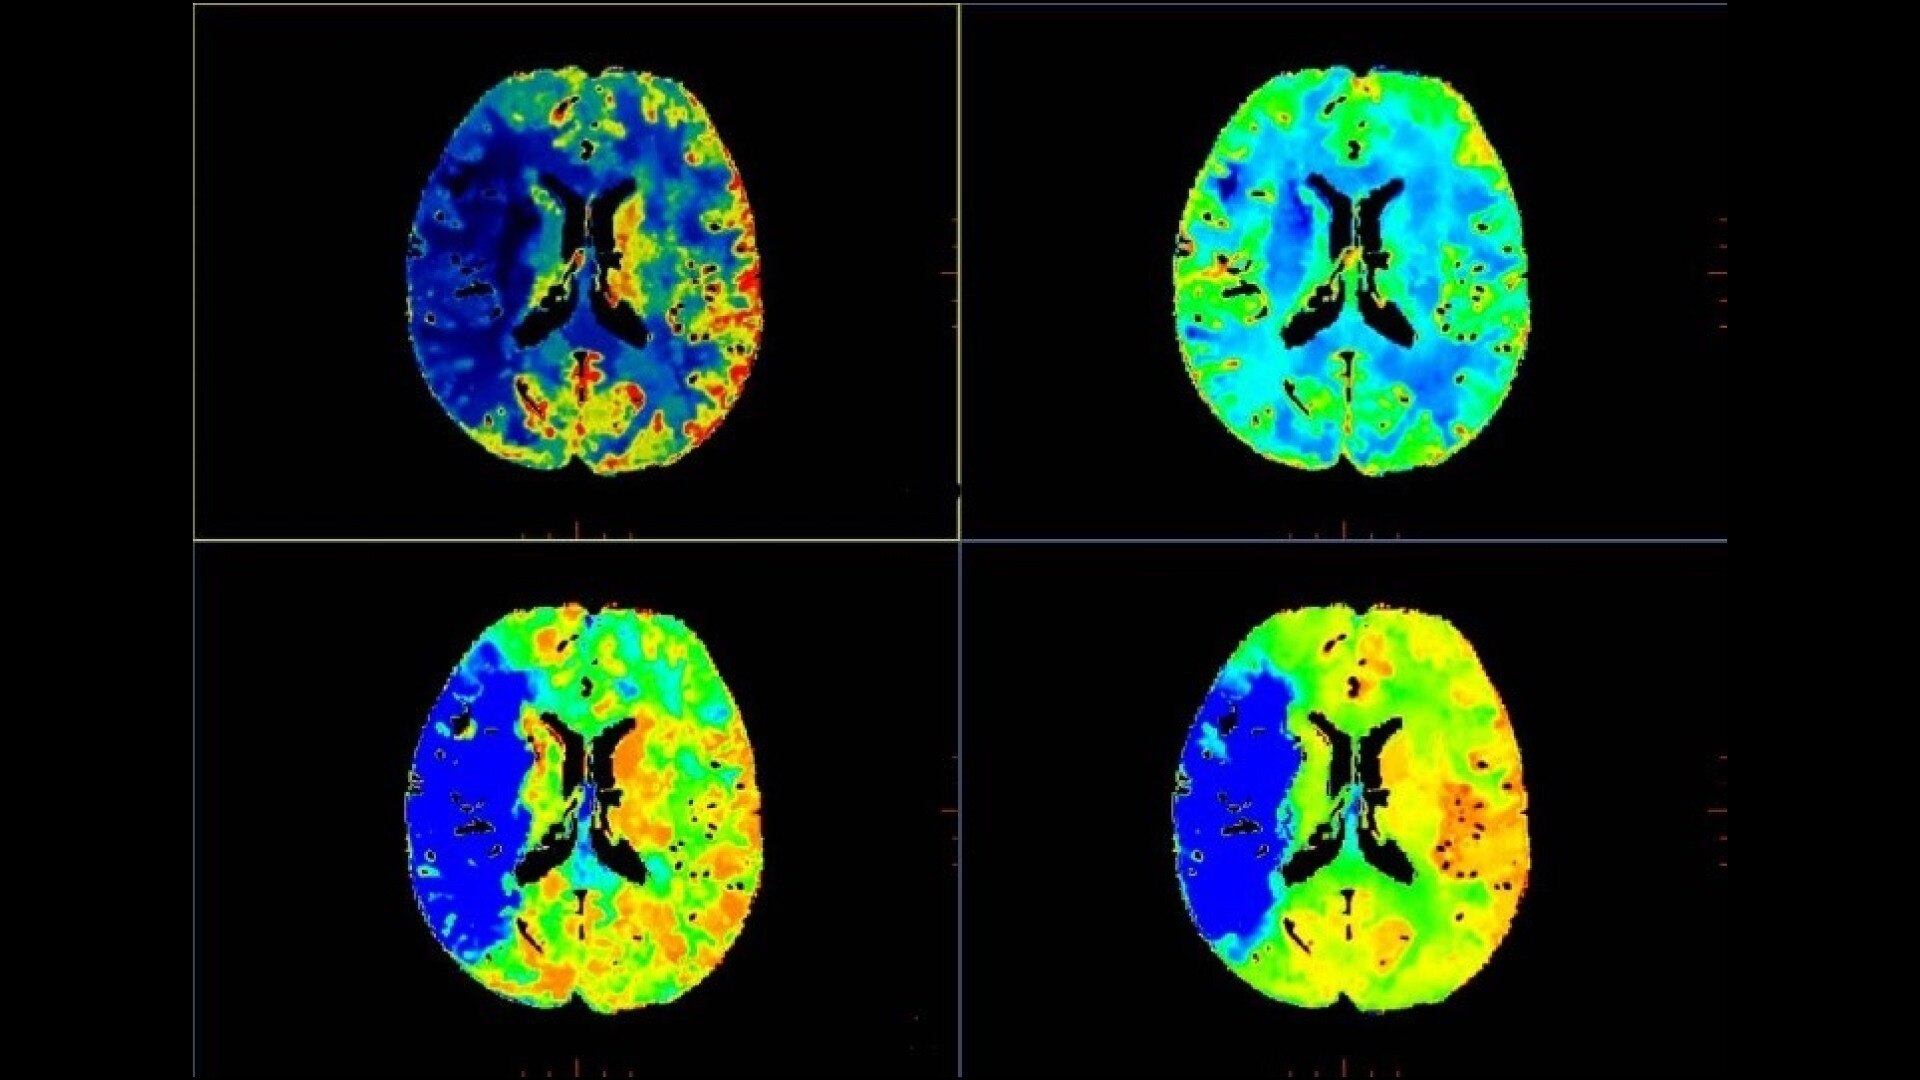

Brain perfusion

Easy-to-use automated workflow for CT stroke and tumor angiogenesis evaluation

Brain stroke protocol

• Image Registration to minimize the effects of patient movement

• Bone Removal to remove the cranium automatically from the dataset

• Deep Learning brain ventricle segmentation to prevent ventricular matter inclusion in quantitative results and improve visual inspection of the maps

• Automated selection of arterial input and venous output. Both can be easily adjusted if needed.

• Automated generation of all functional maps: Blood Flow, Blood Volume, Mean Transit Time, and Transit Time to IRF Peak (Tmax)

• Automatically define the symmetry plane to be used for mirroring ROIs and relative thresholds

• Tissue Classification enables the visualization of regions that are segmented from absolute or relative values, customizable thresholds and user selectable input maps

• Mismatch volume and ratio are calculated from the modified perfusion volume and low perfusion volume ROIs